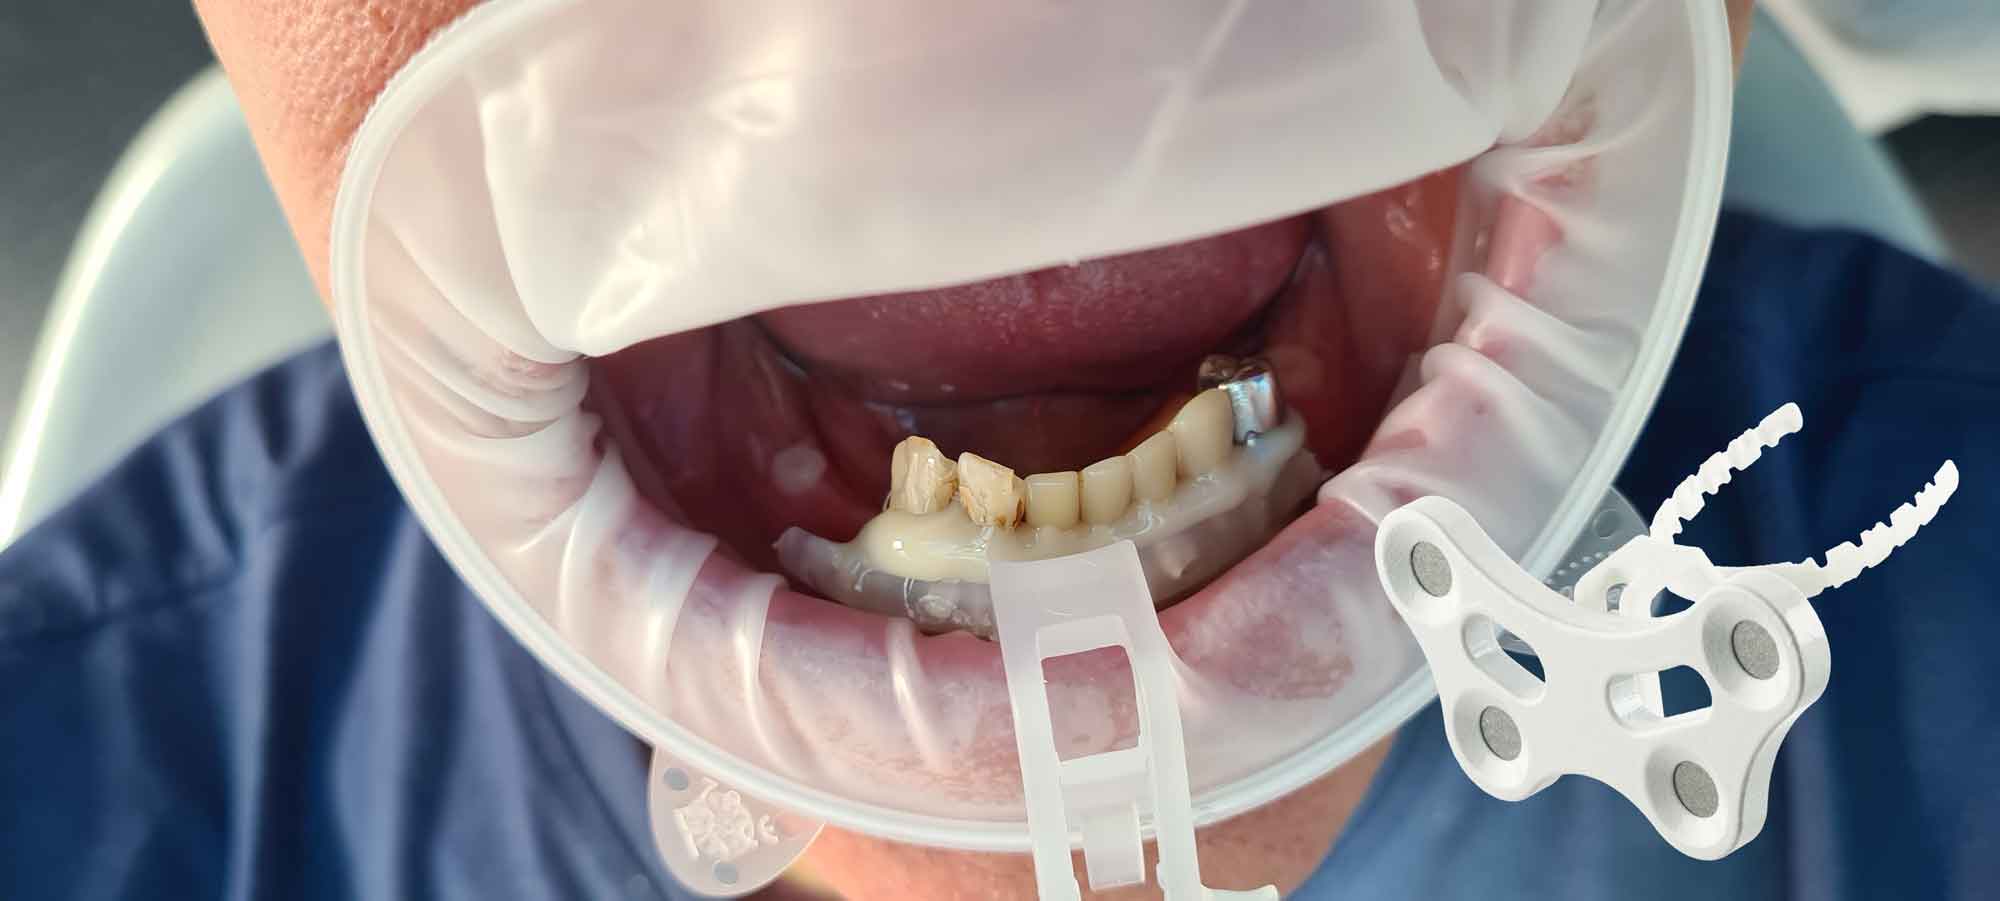

étape 3 – MODJAW – Enregistrement dynamique

En important les fichiers DICOM du patient au lieu des scans IOS, les cliniciens peuvent enregistrer le mouvement de la mâchoire, facilitant ainsi la planification précise du traitement.

Etape 1

Importez les modèles CBCT segmentés en tant que modèles initiaux dans TWIM

Etape 2

Sélectionnez 4 points virtuels sur la mandibule du modèle osseux importé

Etape 3

Fixez la fourchet paraocclusale à la mandibule du patient

Etape 4

Sélectionnez les points précédents dans la bouche du patient à l'aide du Tally (stylet)

Une fois que les mouvements de la mâchoire du patient sont enregistrés, le logiciel TWIM est une aide supplémentaire pour le diagnostic et la planification du traitement.